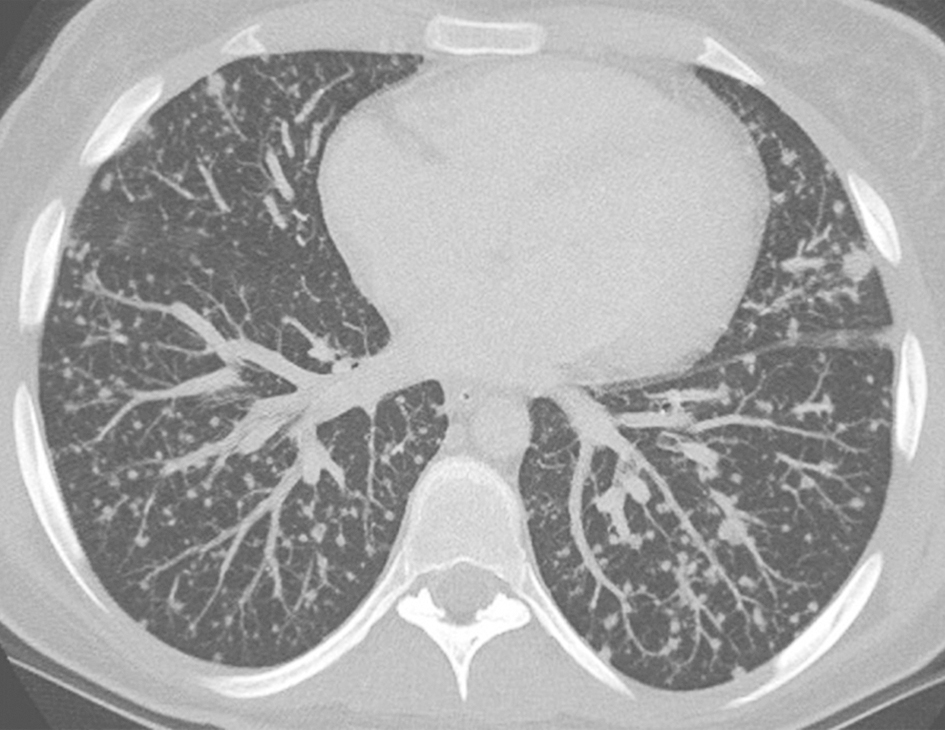

图3粟粒性肺结核胸部CT表现

女性患者,39岁,发热伴胸闷1个月余,病理诊断为粟粒性肺结核。胸部CT可见双肺随机分布的弥漫粟粒性结节